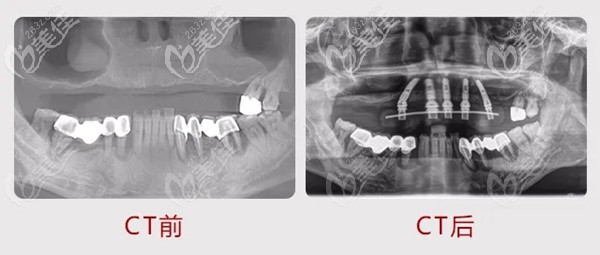

張先生在麥芽口腔術(shù)前術(shù)后拍的CT,當(dāng)時(shí)來(lái)院陳海濱醫(yī)生在檢查后發(fā)現(xiàn)很多牙齒已經(jīng)壞掉,建議拔掉重新種,因?yàn)楹芏嘌例X已經(jīng)沒(méi)有保留的價(jià)值,拔掉之后做種植牙效果會(huì)好一點(diǎn)!